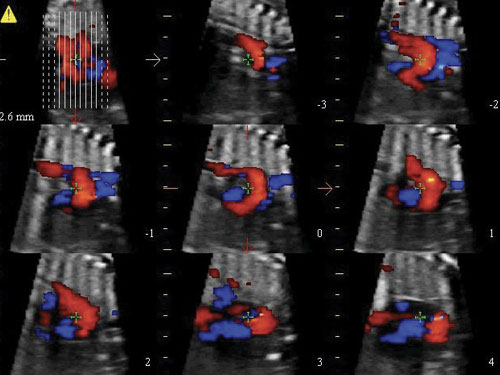

XSTIC: Software pro rekonstrukci plodu XSTIC určený pro volumetrickou rekonstrukci v režimu B a barvě / síle srdečních dutin plodu.

XStrain4D: XStrain4D je technologie sledování, která poskytuje volumetrický model funkce srdce.